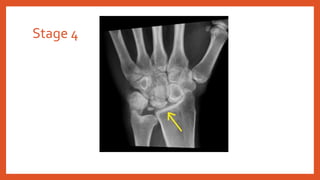

• Stage 4: severe lunate collapse with Radio-carpal and Mid-carpal joint

degenerative changes

Stage 4